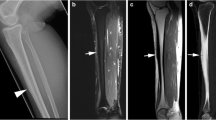

None of the patients had decreased cortical density or endosteal thickening of the fibula on initial or follow-up radiographs. Two of the 14 patients (14.3%) with initial radiographs had a periosteal reaction on the lateral cortex of the fibula (Fig. 1). Five of the 10 patients (50%) with follow-up radiographs had a periosteal reaction on the lateral cortex of the fibula (Fig. 2). The periosteal reaction was located on the distal third of the fibula in 4 patients (80%) and on the proximal third of the fibula in 1 patient (20%). The 1 patient with a periosteal reaction on the proximal third of the fibula also had a fracture line through the lateral fibular cortex. All patients with radiographic abnormalities had Fredericson grade 4 stress injuries on MRI (Figs. 1, 2).

A 13-year-old male basketball player with a 2-week history of proximal fibular pain. a Initial lateral radiograph of the fibula shows faint periosteal reaction (arrows) on the posterior cortex of the proximal fibular diaphysis. b Follow-up lateral radiograph of the fibula 1 month later shows consolidation of the periosteal reaction (arrows). c Corresponding sagittal fat-suppressed T2-weighted fast spin-echo MRI of the fibula performed 1 day after the initial radiographic examination shows periosteal edema (arrows) on the posterior fibular cortex with adjacent intramedullary bone marrow edema (arrowhead). d Corresponding axial fat-suppressed T2-weighted fast spin-echo MRI of the fibula performed 1 day after the initial radiographic examination shows periosteal edema (arrows) on the posterior and lateral fibular cortex with adjacent intramedullary bone marrow edema (small arrowhead). Also note the globular intracortical signal abnormality (large arrowhead) within the posterior fibular cortex

A 23-year-old male football player with a 4-week history of distal fibular pain. a Initial anteroposterior radiograph of the fibula shows no abnormality. b Follow-up anteroposterior radiograph of the fibula 3 weeks later shows periosteal reaction (arrow) on the lateral cortex of the distal fibular diaphysis. c Corresponding coronal fat-suppressed T2-weighted fast spin-echo MRI of the fibula performed 2 weeks after the initial radiographic examination shows periosteal edema (arrows) on the lateral fibular cortex with adjacent intramedullary bone marrow edema (small arrowhead). Also note the globular intracortical signal abnormality (large arrowhead) within the lateral fibular cortex. d Corresponding axial fat-suppressed T2-weighted fast spin-echo MRI of the fibula and e axial T1-weighted spin-echo MRI of the fibula performed 2 weeks after the initial radiographic examination shows periosteal edema (arrows) circumferentially distributed throughout the fibular cortex with adjacent intramedullary bone marrow edema (small arrowhead). Also note the globular intracortical signal abnormality (large arrowhead) within the lateral fibular cortex